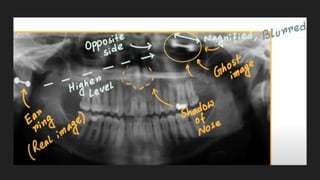

GHOST IMAGES

A ghost image is a commonly observed artifact in an orthopantomogram

whereby a dense, often metallic object is located between the source of

x-ray and the focal centre, resulting in a duplicate 'ghost' image at the

contralateral aspect of the image.